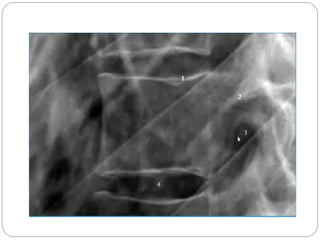

1, Corpo Vertebral (T1). 2, Processo Espinhoso C7. 3, Lâmina do arco vertebral. 4, Processo articular inferior. 5, processo articular superior. 6, Processo Espinhoso C2. 7, Processo odontóide (ou dente do áxis). 8, Arco anterior do atlas (C1). 9, Traquéia

1, Corpo Vertebral(T1). 2, Processo Espinhoso C7. 3, Lâmina do arco vertebral. 4, Processo articular inferior. 5, processo articular superior. 6, Processo Espinhoso C2. 7, Processo odontóide (ou dente do áxis). 8, Arco anterior do atlas (C1). 9, Traquéia